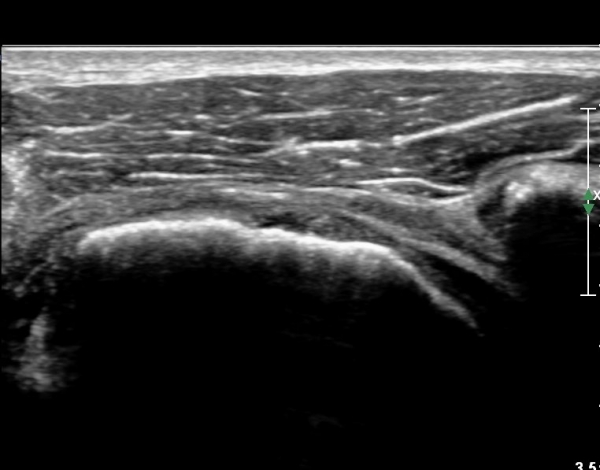

ÃÊÀ½ÆÄ ¼Ò°ß :  È¸Àü±Ù°³°£°Ý °Ë»ó»ó ±Ø»ê°ÇÀº Á¤»ó¼Ò°ßÀ» º¸À̳ª °ß°©ÇϱٰÇÀº Àú¿¡ÄÚ ¿¬°á¼º ¼Ò½ÇÀÌ

º¸¿© °ß°©ÇÏ±Ù°Ç ÆÄ¿­ÀÌ ÃßÁ¤µÈ´Ù(»çÁø 1). ŽÃËÀÚ¸¦ ¾à°£ ¾Æ·¡·Î À̵¿ÇÑ ÈÄ